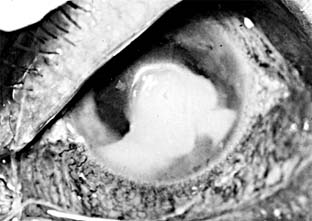

Unlike recurrent HSV keratitis that usually affects only the epithelium, VZV keratitis affects the stroma and anterior uvea at onset. The epithelial lesions are blotchy and amorphous except for an occasional linear pseudodendrite that only vaguely resembles the true dendrites of HSV keratitis. Stromal opacities consist of edema and mild cellular infiltration and initially are subepithelial. Deep stromal disease can follow with necrosis and vascularization (Figure 6-6). A disciform keratitis sometimes develops and resembles HSV disciform keratitis. Loss of corneal sensation is always a prominent feature and often persists for months after the corneal lesion appears to have healed. The associated uveitis tends to persist for weeks or months, but with time it eventually heals. Scleritis (sclerokeratitis) can be a serious feature of VZV ocular disease.

Figure 6-6

Figure 6-6: Herpes zoster keratitis.